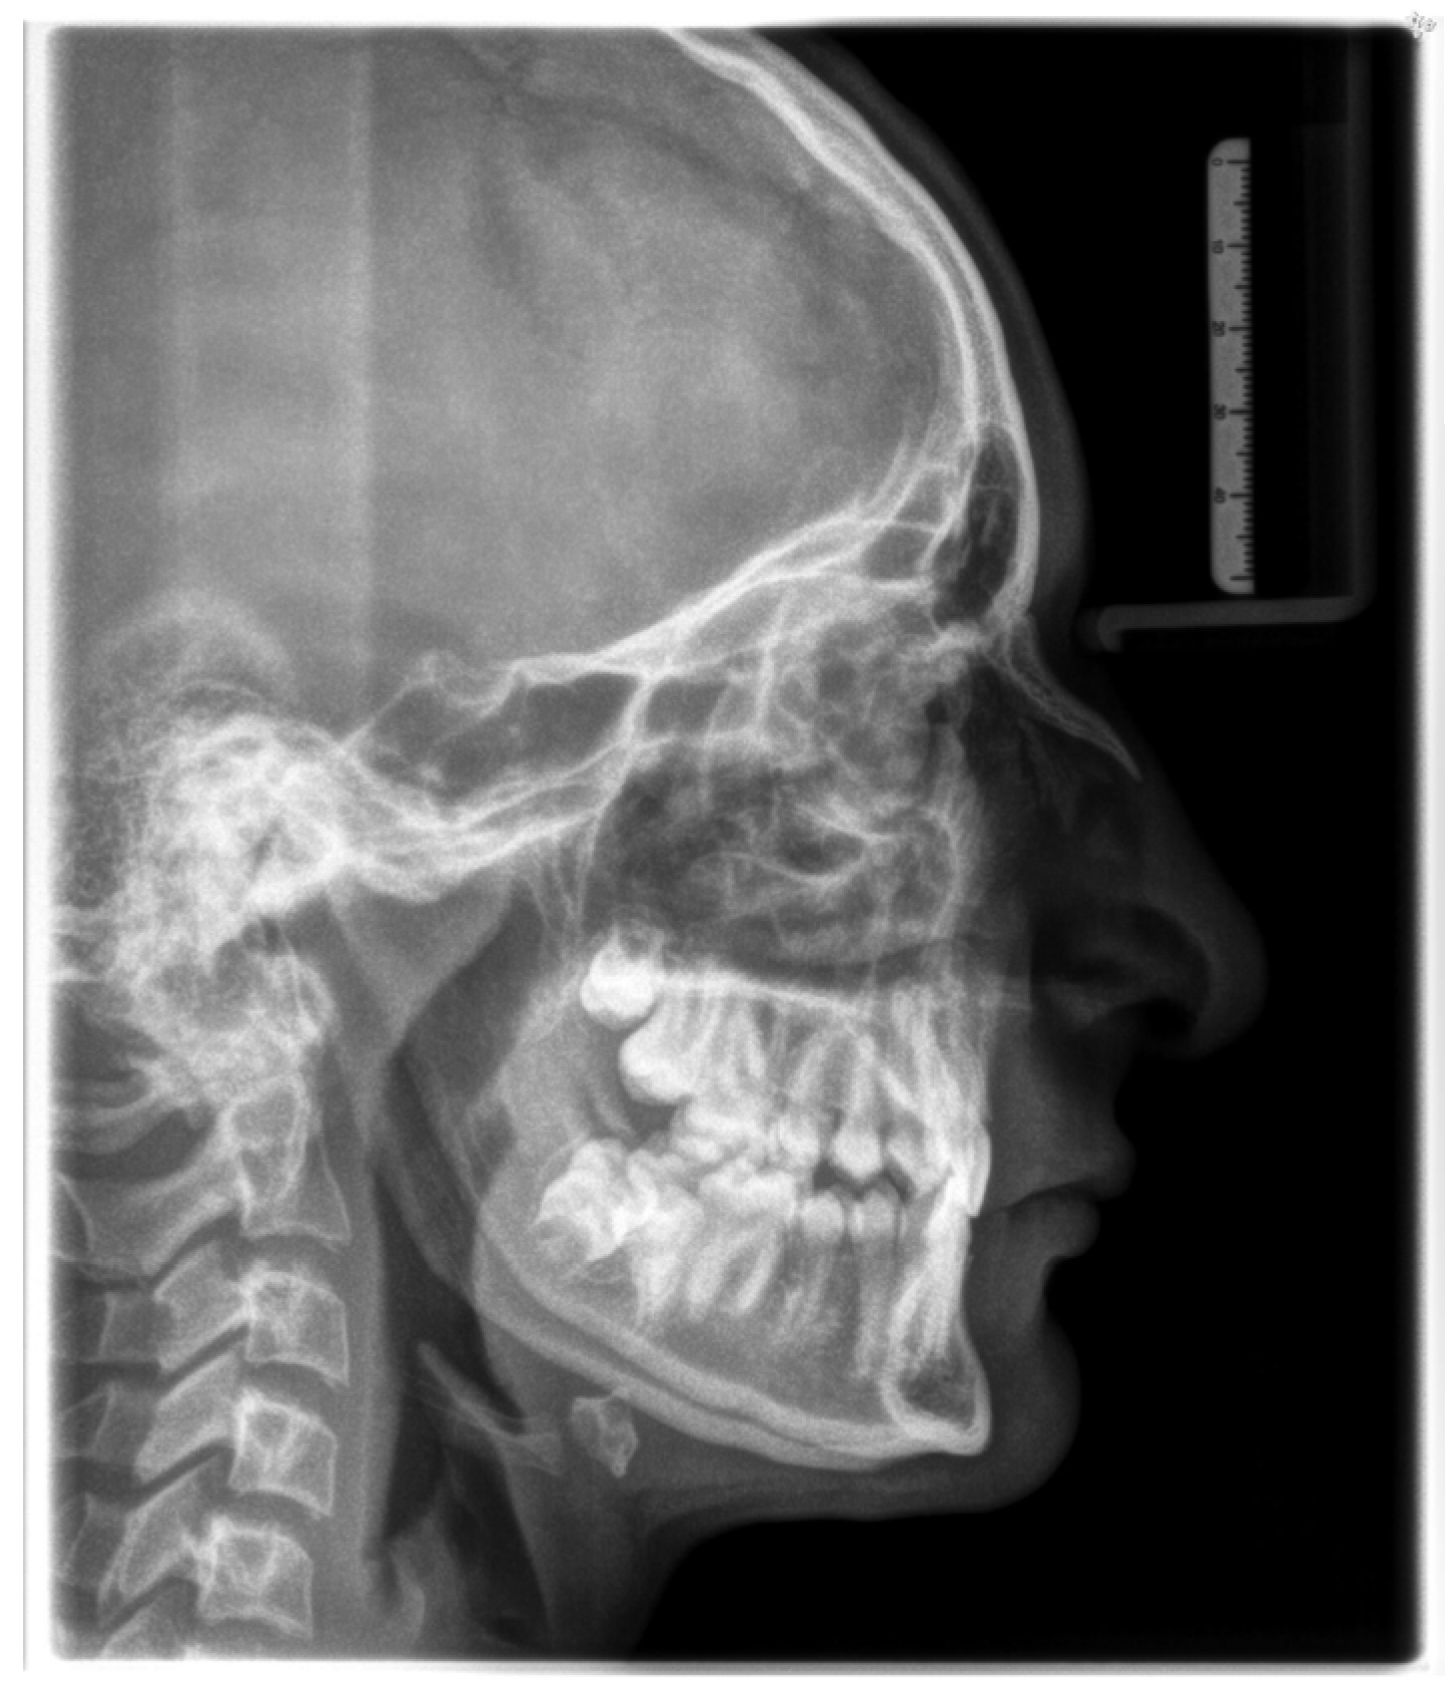

| Description | Cephalometric Measurements | Value | Mean | SD |

|---|---|---|---|---|

| Maxilla to Cranial Base | SNA | 78.67 | 82.00 | 3.00 |

| NL-NSL | 11.29 | 8.00 | 4.00 | |

| Mandible to Cranial Base | SNB | 79.03 | 80.00 | 3.00 |

| ML-NSL | 25.82 | 28.00 | 5.00 | |

| Maxilla to Mandible | ANB | −0.36 | 3.00 | 2.50 |

| WITS [mm] | −2.40 | 0.00 | 2.00 | |

| ML-NL | 14.53 | 20.00 | 7.00 | |

| Maxillary Dentition | U1-NA [mm] | 1.50 | 3.70 | 2.00 |

| U1-NA | 16.32 | 21.00 | 4.00 | |

| Mandibulary Dentition | L1-NB [mm] | −1.98 | 3.80 | 5.00 |

| L1-NB | 2.44 | 24.00 | 4.00 | |

| Soft Tissue | Nasio-labial angle | 89.72 | 110.00 | 7.00 |

| SNPg | 81.49 | 81.00 | 3.00 | |

| N-S-Ba angle | 138.49 | 132.00 | 4.00 | |

| Gn-tgo-Ar angle | 133.52 | 122.00 | 7.00 | |

| NB-H angle | 6.09 | 9.00 | 3.00 | |

| U1-L1 | 161.60 | 133.00 | 8.00 | |

| Pg-NB [mm] | 4.91 | 2.30 | 2.00 | |

| N-Sp’/Sp’-Gn [%] | 88.21 | 80.00 | 7.00 |